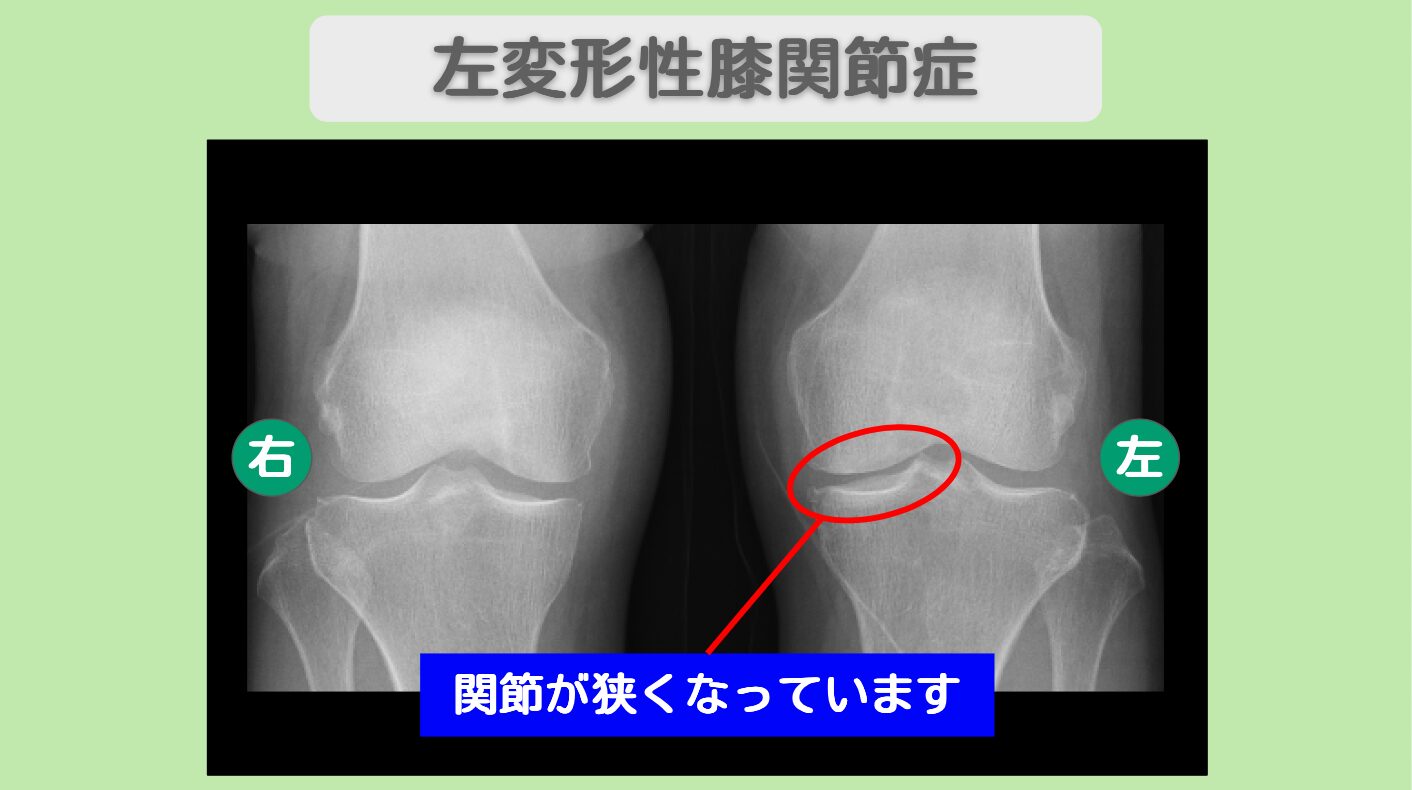

MRI・レントゲン所見